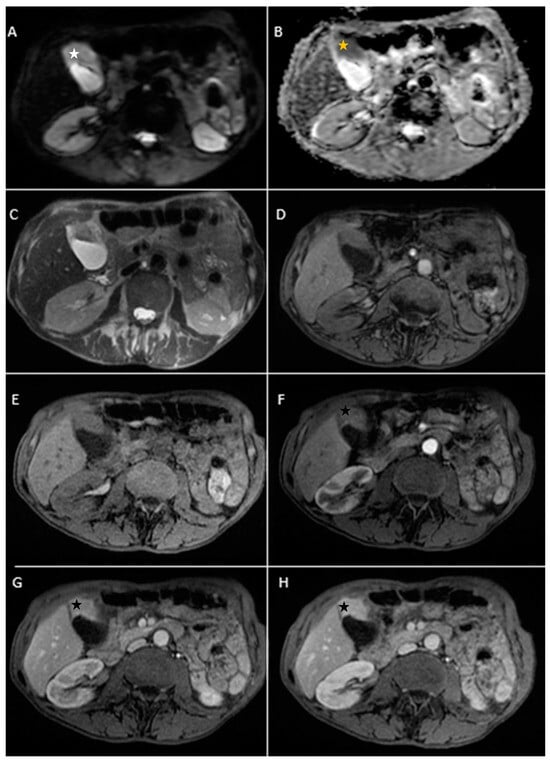

Figure 5. Abdominal MRI vividly illustrating synchronous gallbladder and biliary tract carcinoma with multiple large lymphadenopathies localized in the hepatic hilum, surrounding the cephalic region of the pancreas and in the celiac region. (A) Axial T2-weighted FS showed significant intrahepatic biliary dilatation in both hepatic lobes (yellow arrow). (B) Axial T2-weighted FS showed hypointense intraluminal gallbladder mass (white star) and multiple large lymphadenopathies. (C) Axial diffusion-weighted imaging (DWI B800) showed irregular, asymmetrical thickening of the walls of the intrahepatic bile ducts with high signal intensity suggestive of cholangitis (green arrow). (D,E). DWI B800 highlighted the gallbladder mass; inhomogeneous areas of high signal (yellow stars). (F) Coronal 3D MRCP showed enlarged gallbladder with an intraluminal gallstone and dilated intrahepatic and extrahepatic biliary tree. (G,H). On apparent diffusion coefficient (ADC) map, the gallbladder mass is dark, illustrating markedly diffusion restriction (green star). Multiple large lymphadenopathies are also observed mainly in the lombo-aortic region, in the cephalic pancreatic region and in the hepatic hilum (blue arrow). (I) Axial T1-weighted image showing hypointense irregular tumoral gallbladder mass (white star). (JL). Axial contrast-enhanced (arterial phase followed by venous phase) T1-weighted image showing rim-enhancing of the tumoral gallbladder mass (white arrow).

Contrast-enhanced emergency CT was performed (Figure 4), which richly highlighted a large heterogeneous intraluminal gallbladder mass, localized in the gallbladder fundus, measuring 58/34 mm, irregular, peripheral contrast enhancement on arterial and venous phase and with central hypodensity suggestive of areas of necrosis, extending to the surrounding liver (segment V) (Panel A and Panel C). CT showed a gallstone (17 mm) wedged in the gallbladder neck and intrahepatic biliary dilatation (Panel C and D). The common bile duct was dilated due to the presence of a possible tumoral extension to biliary tract or by the compressive effect of the multiple hilar lymphadenopathies; mesenteric, celiac and retroperitoneal lymphadenopathies with areas of necrosis, measuring up to 25/15 mm were also noted (Panel B). Abdominal contrast-enhanced MRI was performed (Figure 5).

Furthermore, endoscopic retrograde cholangiopancreatography showed a stenosis (with the length of 14–15 mm) at the middle third of the major biliary tract, therefore a stent was placed.

In this case, the probable diagnosis was of synchronous gallbladder and biliary tract carcinoma with multiple large lymphadenopathies localized in the hepatic hilum, surrounding the cephalic region of the pancreas and in the celiac region.

Endoscopic ultrasound-guided fine-needle aspiration (EUS-FNA) for gallbladder tissue was performed. Histopathology showed small cell neuroendocrine carcinoma of the gallbladder. Immunohistochemical stains were positive for CK7, synaptophysin (Syn) and chromogranin A (CgA), and the Ki-67 indexes were over 97% cells.